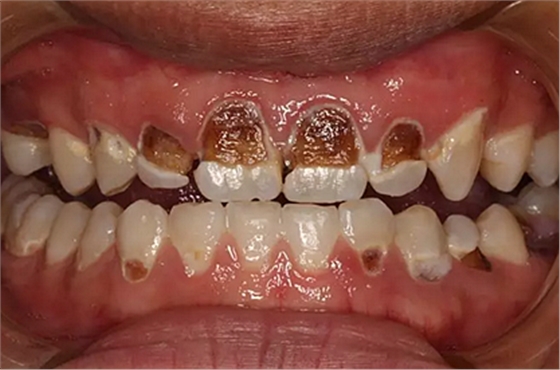

我們的主人今年才25歲,可卻從很小的時候就嗜好喝可樂等碳酸飲料,幾年下來,讓我們兄弟姐妹們整天浸在碳酸里受這蝕骨之痛,原本皎潔的外貌如今早己經(jīng)是腐蝕不堪、丑陋無比,更有甚者,一些兄弟姐妹們已經(jīng)病入膏肓,被病痛折磨奄奄一息。

下面是醫(yī)生眼中和ct下的我們

一身病痛啊

牙結石、牙齦炎癥、牙體殘缺、慢性牙髓炎、蛀牙......

才二八芳華的我們

已經(jīng)滿目蒼夷

再來看看曾經(jīng)的我們